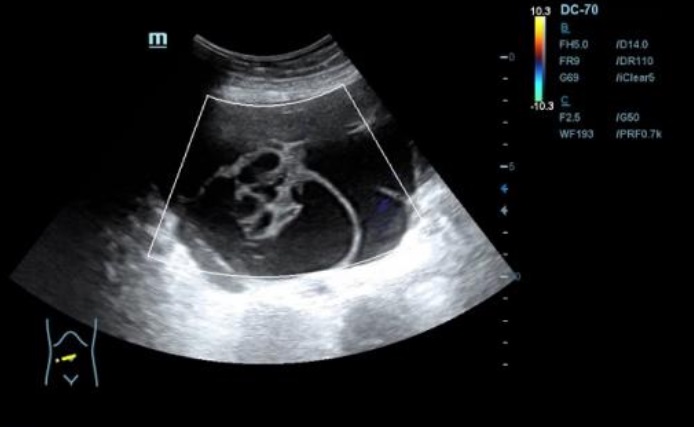

Ecografía: se observa presencia de líquido ascítico, e imagenes en hipomesogastrio hipo e hiper ecogénicas, tabicadas algunas, con efecto masa, con vascularizacion al Doppler que sugieren carcinoma de ovario.

Neoplasia de ovario bilateral con carcinomatosis peritoneal y omental, implantes peritoneales y subcapsulares hepáticas y abundante ascitis.